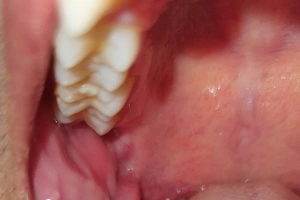

Partially erupted tooth causing cheek biting